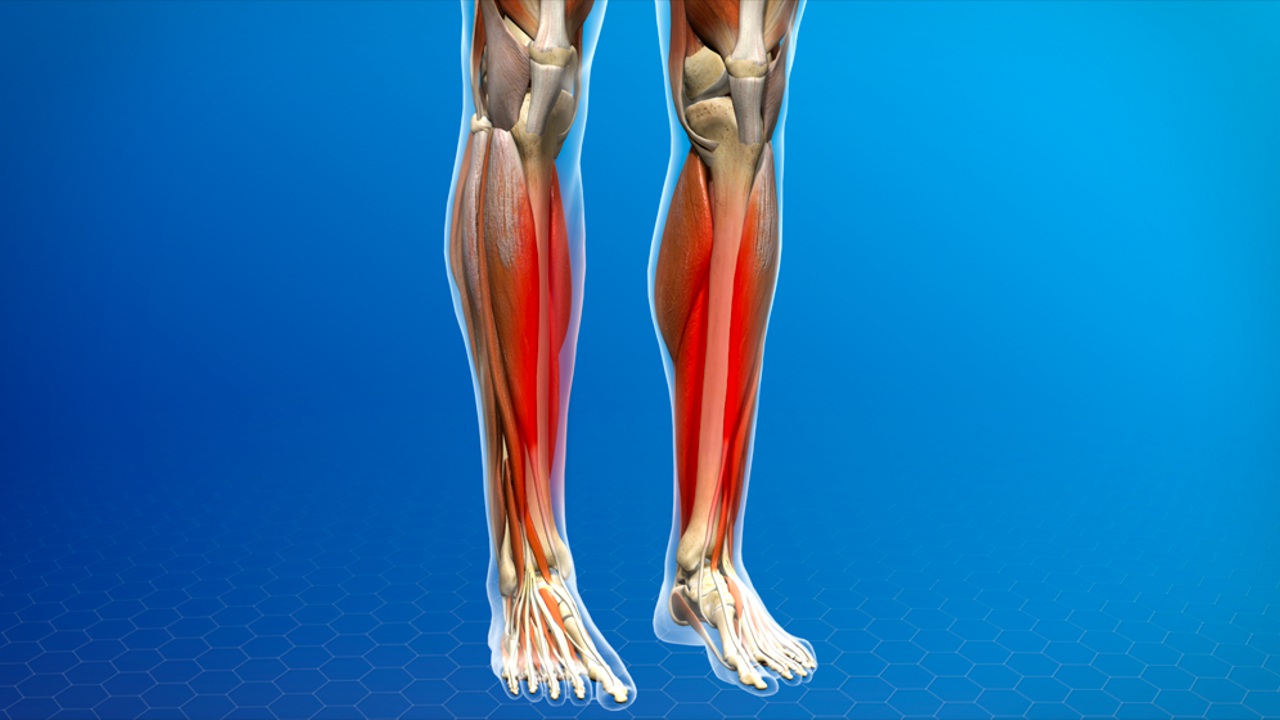

شین اسپلینت (Shin Splints)

شین اسپلینت (Shin Splints) یا سندرم استرس تنشی تیبیال (Medial Tibial Stress Syndrome) یکی از آسیبهای شایع در میان دوندگان، ورزشکاران و کسانی است که فعالیتهای ورزشی مکرر با فشار زیاد روی ساق پا دارند. این اختلال ناشی از فشار و استرس مکرر بر روی استخوان تیبیال و تاندونهای مجاور آن است که منجر به التهاب و درد در ناحیه میانی ساق پا میشود.

علائم اصلی شین اسپلینت شامل درد و حساسیت در ناحیه داخلی ساق پا است که معمولاً در طول یا پس از فعالیتهای ورزشی بروز میکند. در مراحل اولیه، درد ممکن است فقط هنگام دویدن یا راه رفتن شدید احساس شود، ولی با پیشرفت بیماری، درد حتی در حالت استراحت نیز پدیدار میشود. همچنین، ناحیه آسیب دیده ممکن است ملتهب و حساس به لمس شود و برخی افراد گزارش میکنند هنگام لمس، احساس سوزش یا گزگز داشتن دارند.